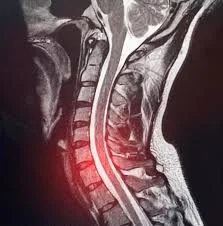

MRI scan of a human neck and upper spine showing vertebrae and spinal cord with highlighted area indicating possible injury or abnormality.

"Two surgeons told me I needed a Discectomy. The Ripped Santa proved them wrong."

"I had a herniated cervical disc (C6/C7) and had been struggling with a physical 'challenge' since October. I saw every medical professional available, and they all said the same thing: surgery. I wasn't ready to accept that.

It wasn't until I started following The Ripped Santa's suggestions that the needle finally moved. He sold me on specific recovery protocols like the sauna and adjusted my mobility work. In just a month and a half, I went from chronic pain to 85-90% healed. I truly believe it was his guidance that healed me when doctors couldn't. Next stop: getting back to the heavy weights."